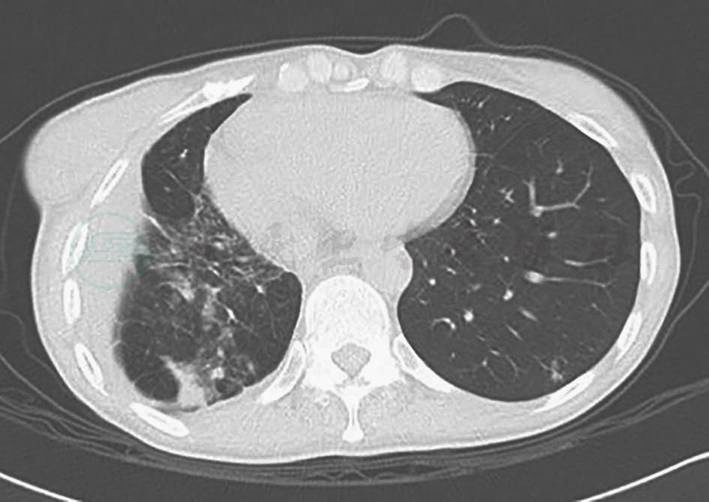

2011年1月患者因发热、咳嗽及咳痰入院,体温最高可达39℃,伴全身肌肉疼痛,以近端肌肉为主,无各系统感染征象,无盗汗、消瘦,无口干、眼干,血培养、痰找抗酸杆菌、痰细菌及真菌培养均阴性,结核分枝杆菌纯蛋白衍生物试验阴性,血结核分枝杆菌-聚合酶链反应(PCR)阴性。支气管灌洗液细胞计数及分类:巨噬细胞20.5%,分叶核细胞66%,淋巴细胞12%,嗜酸性粒细胞1.5%,细胞总数1.07×106/ml。支气管肺泡灌洗液涂片:可见大量退变的中性粒细胞,大量肺泡上皮细胞及吞噬细胞,少量红细胞及嗜酸性粒细胞,散在淋巴细胞。类风湿因子、抗环瓜氨酸多肽抗体、抗角蛋白抗体和抗核周因子抗体均阳性,红细胞沉降率、C反应蛋白升高,胸部CT示“右中肺磨玻璃影,机化性肺炎”(图2)。先后予莫西沙星、阿奇霉素、头孢他啶、亚胺培南及伊曲康唑规律性抗感染治疗均无效,考虑患者为“类风湿关节炎肺损害、机化性肺炎”,给予甲泼尼龙40mg/d,约2~3天后症状好转,1周后复查胸部CT好转,此后改为口服泼尼松40mg/d,3周后减为35mg/d,并开始加用静脉环磷酰胺400mg/2周。泼尼松减量为35mg/d 1周后(环磷酰胺累计量为400mg),上述症状再次出现,为进一步诊治收入院。既往史、个人史和家族史无特殊。

图2 2011年1月胸部CT示右中肺磨玻璃影,机化性肺炎